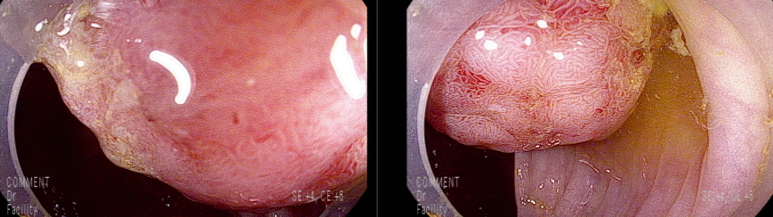

마지막 유경성 거대 용종을 제외하고 점막 소구 패턴(pit pattern)이 불규칙하게 관찰되어(Vi) 고등급의 선종 혹은 점막암을 의심하여 충분히 융기시켜 경계가 확실히 포함되고 한조각으로 완전 절제하기 위해 넓게 절제함

7-8 mm 크기

9 mm 크기